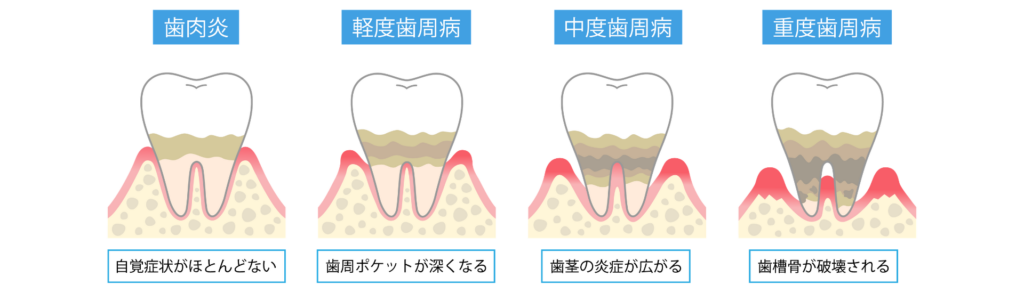

歯周病はいつの間にか進行していきます

歯周病がこれほどまでに蔓延している最大の理由は初期段階では、自覚症状がほとんどないことにあります。

歯周病の正体は歯垢(プラーク)に含まれる細菌による感染症です。

歯と歯茎の境目に溜まった細菌が毒素を出し、歯茎に炎症を起こします。

やがて炎症は深部へと広がり、歯を支える土台である「歯槽骨(しそうこつ)」を破壊していきます。